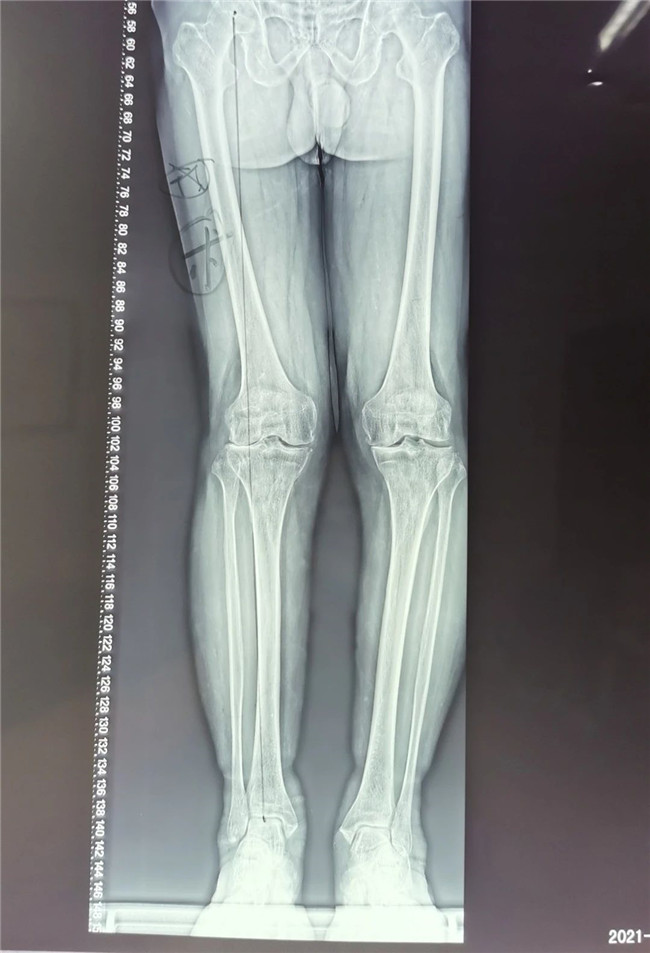

▲右膝關節(jié)外翻畸形 ▲

75歲的張大爺右膝關節(jié)疼痛已有數(shù)年,近半年來,右膝疼痛加重,平地行走時也感覺困難,疼痛導致右膝不敢完全負重,走路呈現(xiàn)明顯的跛行姿態(tài)。不堪忍受病痛折磨的病人前來我院骨科中心找到羅軍主任求醫(yī)。

接診后羅軍主任詳細檢查病人,發(fā)現(xiàn)病人疼痛癥狀主要集中在膝關節(jié)外側(cè)間室,右下肢有明顯外翻畸形。這些癥狀都是單髁置換的適應癥。雙下肢全長攝片和右膝內(nèi)翻、外翻位攝片顯示,膝關節(jié)外側(cè)間隙消失,膝外翻畸形,果不其然印證了上述臨床表現(xiàn)。收治入院后,羅主任團隊決定為患者實施微創(chuàng)膝關節(jié)外側(cè)單髁置換術(shù),盡全力為張大爺解除病痛的折磨。